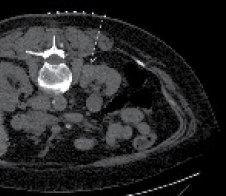

In an ideal case, there are three CT scans performed. The first CT scan is performed in the prone position using IV contrast (50% of standard dose) to plan the procedure. It is important to pay attention to surrounding structures as abdominal contents could have shifted compared to a supine CT scan. Patients with renal insufficiency can be challenging as contrast is usually avoided. Therefore, one must rely on cortical changes in the non-contrast phase to delineate the lesion, Figure 1. The trajectory of the probe is planned and measured. It is of high importance to be able to insert the probe as straight as possible (perpendicular to the skin) toward the mass. If a mass is quite medial as shown in Figure 1, it is best to plan the placement of the probe slightly lateral off the paraspinal muscles to avoid pain.

Figure 1. Non-contrast planning image of patient with renal insufficiency. Notice the cortical and contour changes that help delineate the mass. Typically, it is best to come down as perpendicular on the mass as possible. With lesions located very medial, it is best to come slightly lateral off the paraspinal muscles when planning the trajectory of the probe (dashed line) to avoid pain.